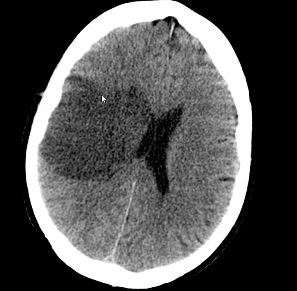

Always do a CT head.

Why do we do a CT head?

If there is a bleed or not.

We do not want a bleed.

We try to exclude the 10% of haemorrhagic strokes

Features of an acute CT head.

Ischaemic area of brain is not visible early on however a bleed will show up.